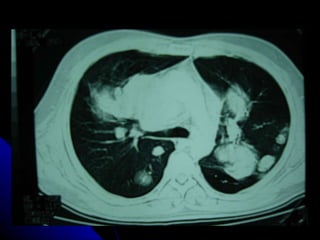

SÍNDROME PARENQUIMAL Conjunto de signos radiográficos que traducen una lesión en el parénquima pulmonar, la  que  puede ser localizada o difusa. Didácticamente podemos dividirlo en tres tipos: Alveolar Intersticial Mixto ( alveolo intersticial)

SÍNDROME PARENQUIMAL Conjuntode signos radiográficos que traducen una lesión en el parénquima pulmonar, la que puede ser localizada o difusa. Didácticamente podemos dividirlo en tres tipos: Alveolar Intersticial Mixto ( alveolo intersticial)